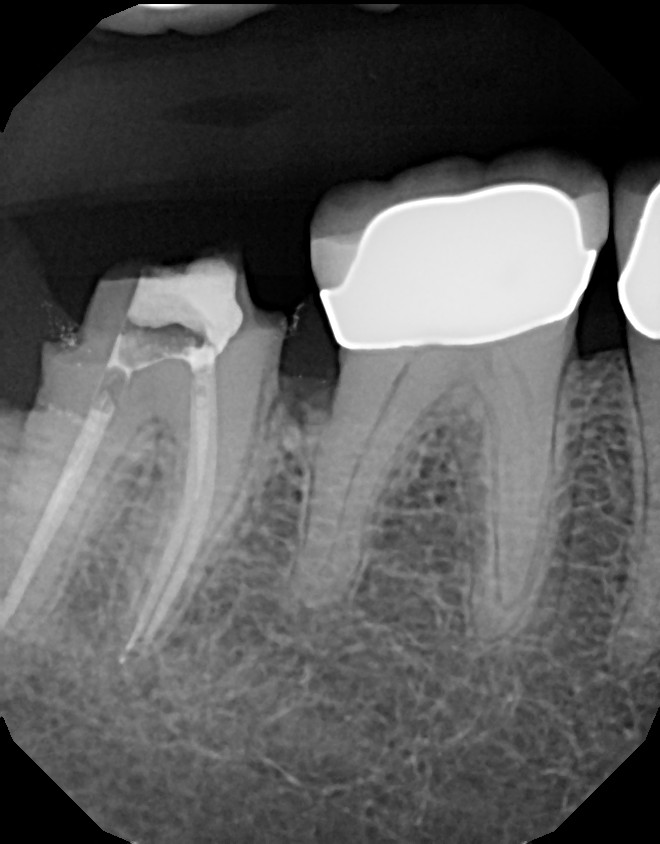

Below are pictures of a recent case of mine. This 10+ year old crown that developed decay (cavity) around the margin where tooth meets crown. Always pay attention to sensitivity around fillings and crowns and advise your dentist when symptoms develop, so you can stay away from roots canals. In this particular case, root canal was required because the decay reached too close to the nerve.